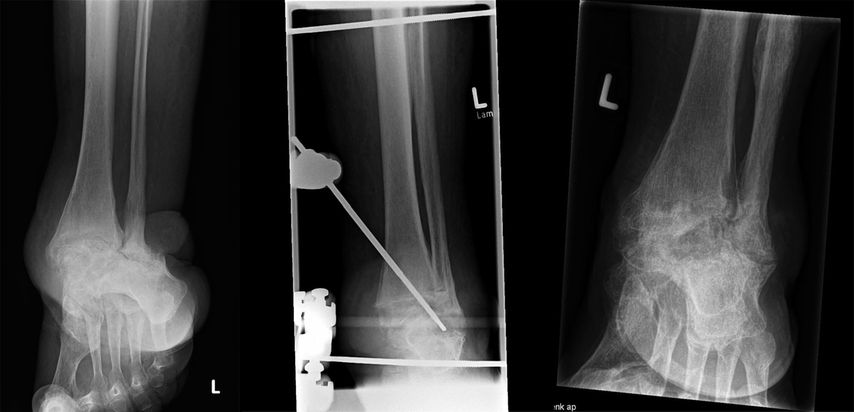

Das Skelett kann nach einem adäquaten Trauma atrophisch (Sanders-Typ 1) oder pseudarthrotisch (Mittelfußfrakturen) sein. Insuffizienzfrakturen betreffen häufig den Kalkaneus (Sanders-Typ 5) oder die Metatarsalmetaphyse (Sanders-Typ 2); Kompressionsfrakturen des Talus (Sanders-Typ 3, 4) ähneln einer avaskulären Nekrose im Spätstadium. Darüber hinaus können ein Luxationstyp (vor allem Sanders-Typ 2 und 3), ein klassischer Frakturtyp („Bag of Bones“) und eine Vielzahl von Mischtypen beobachtet werden.

Eine stabile Fixierung des Fußes wird durch zwei weitere „full pins“ erreicht, von denen einer durch den Tuber calcanei und der zweite durch die distalen Mittelfußknochen (retrokapital) geführt wird, wo diese Knochen normalerweise in einer Ebene liegen. Während das Einsetzen des Fersenbein-Pins sicher und einfach ist, kann das Bohren des Mittelfuß-Pins durch alle 5 Knochen technisch anspruchsvoll sein. Im Gegenzug sorgen mehrere Corticales für eine ausgezeichnete Stabilität, sodass die Fixierung des ersten Strahls zusammen mit zwei kleinen Mittelfußknochen eine zufriedenstellende Fixierung bietet; ein oder zwei zusätzliche Knochen verbessern die Steifigkeit. Zwei Stangen, in der Regel 300mm lang, sind an den beiden Fußstiften befestigt. Ein Verbindungssteg unterhalb der Ferse ergibt zusammen mit den Stegen an beiden Seiten des Fußes die Form eines „U“. Die Verbindung der 4Tibiastäbe mit dem Pedal-U-Rahmen führt schließlich zu einer Box-Konfiguration, die in allen geometrischen Ebenen den gleichen Widerstand gegen Verformung bietet.

Durch die Verwendung desselben Satzes von Stiften, Stäben und Klammern bietet das Box-Frame-Design Anpassungsmöglichkeiten für die Rekonstruktion des Mittelfußes oder des Knöchels. Bei einem Charcot-Sprunggelenk ist der Fuß zunächst in seinem U-förmigen Rahmen fixiert. Gegenläufige Bewegungen der Stäbe auf beiden Seiten des Fußes ermöglichen die Supination oder Pronation des Vorfußes im Verhältnis zum Rückfuß. Danach wird der Fuß in die korrigierte Position manövriert. Außerdem kann eine Kompression erreicht werden, indem der Fuß-U-Rahmen proximal an den 4 Tibiastäben entlang nach proximal geschoben wird, bis eine (leichte) Biegung der Pedalstifte nach oben festgestellt wird. Die Kompression darf nicht übertrieben werden, um eine reversible, elastische Verformung der Pins, nicht aber eine irreversible plastische Verformung zu erreichen. Federstahl mit einer hohen Elastizitätsgrenze ist daher das optimale Pinmaterial.

Ein weiterer Nachteil ist der große Abstand zwischen der Fixierung in der proximalen Tibia und dem Fuß. Wenn das Sprunggelenk oder das subtalare Gelenk rekonstruiert werden muss, kann es schwierig sein, die Translationsbewegung an der Fragmentstelle zu eliminieren. Da die Scherkräfte, die mit der Fragmenttranslation einhergehen, der Frakturheilung abträglich sind, sind zusätzliche Fixierungselemente erforderlich, um eine angemessene Stabilität zu erreichen. Zu diesem Zweck können am Rahmen befestigte Apex-Pins (mit distalem Gewinde) mit oder ohne Verbindung zum Rahmen verwendet werden.